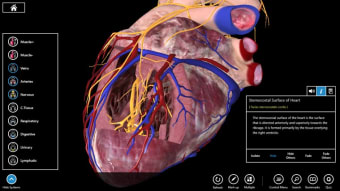

Untuk mahasiswa kedokteran khususnya, Essential Anatomy adalah alat referensi yang luar biasa. Model 3D memungkinkan Anda untuk melihat dan memeriksa bagian tubuh manusia dari sudut mana pun memberikan detail luar biasa yang biasanya hanya dapat Anda alami melalui pembedahan.

Jika Anda perlu menemukan tulang, organ tertentu atau otot, Anda cukup menelusuri berdasarkan bagian tubuh dan Essential Anatomy akan menyorot dengan tepat di mana mereka berada dengan deskripsi bermanfaat dari setiap bagian. Satu-satunya hal yang kurang adalah animasi organ dan otot yang sedang beraksi.

Essential Anatomy sangat mudah digunakan. Fungsi pencarian adalah yang paling Anda butuhkan jika Anda sedang belajar meskipun Anda dapat bersenang-senang hanya dengan menjelajahi dan memutar tubuh. Anda dapat melepaskan lapisan otot dan jaringan untuk mengungkapkan apa yang ada di bawahnya, yang memberi Anda gambaran yang lebih baik tentang cara kerja tubuh daripada hanya membacanya di buku.

Selain itu, ada Alat penanda jika Anda hanya ingin menyimpan bagian tertentu yang ingin Anda kembalikan nanti dan Anda dapat mengisolasi tampilan tubuh berdasarkan jenis bagian (misalnya otot, arteri, vena, dll.).